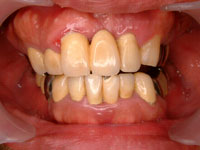

服用前の写真です。上の前歯からウミが出ています。歯茎は赤く腫れ上がり、歯周病が進んでいます。